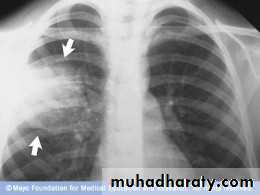

1-Lobar pneumonia‘referring to homogeneous consolidation of one or more lung lobes, often with associated pleural inflammation.

@Radiological examination usually provides confirmation of the diagnosis. In lobar pneumonia, a homogeneous opacity localized to the affected lobe or segment usually appears within 12-18 hours of the onset of the illness. Radiological examination is helpful if a complication such as parapneumonic effusion, intrapulmonary abscess formation or empyema is suspected :@Sputum: direct smear by Gram and Ziehl-Neelsen stains. &Culture and antimicrobial sensitivity testing